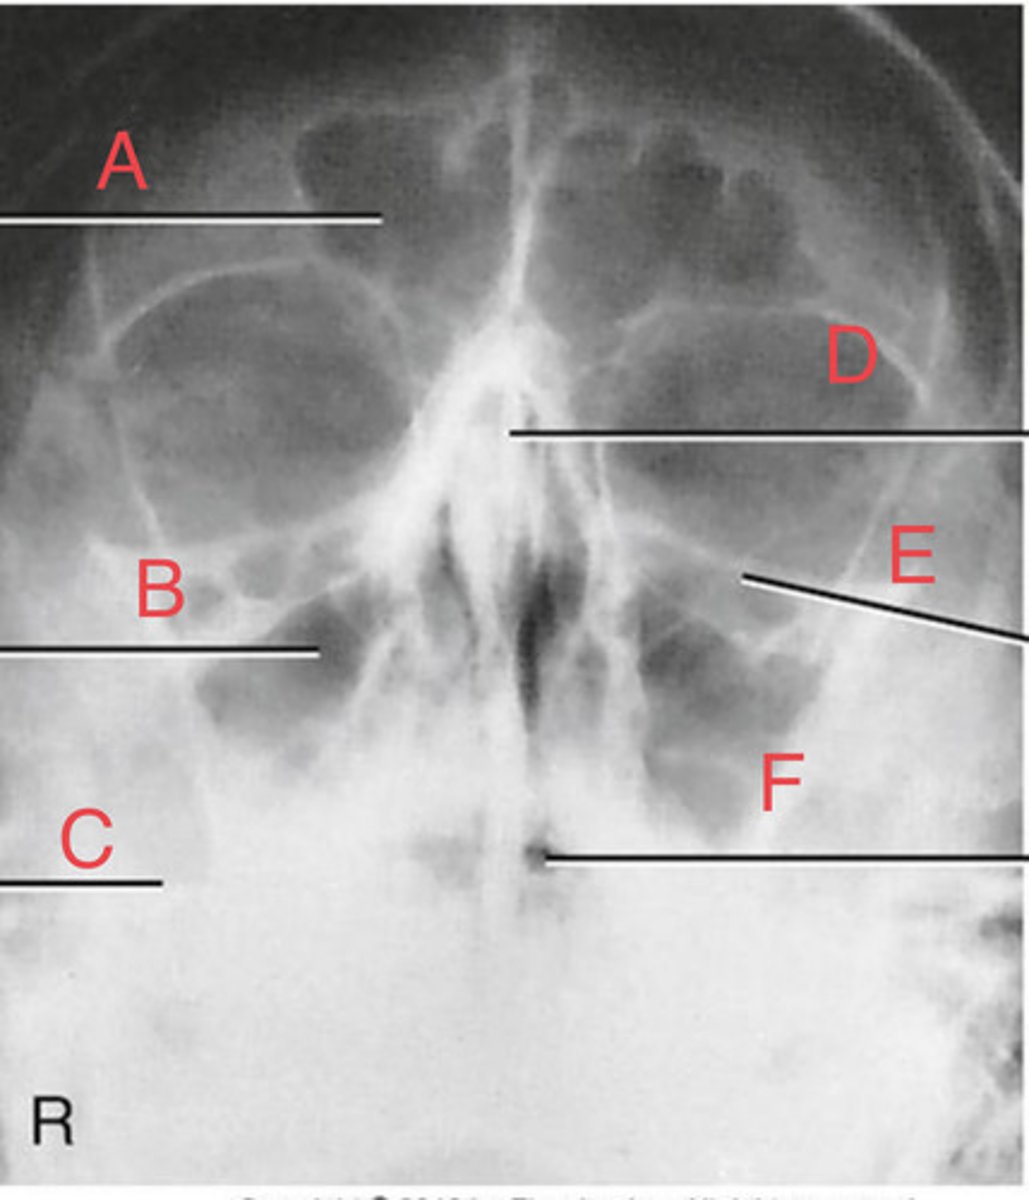

Waters sinus method

What projection?

r. frontal sinus of the frontal bone

A.

R. Maxillary sinus of maxilla

B.

R. petrous ridge of temporal bone

C.

bony nasal septum

D.

L. inferior orbital fissure of sphenoid bone

E.

Sphenoid sinus of sphenoid bone

F.

bony nasal septum

E.